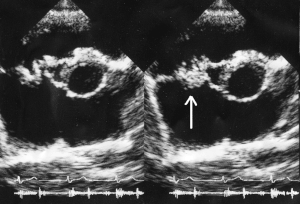

-

Ultrasound showing infectious endocarditis[40]

Ultrasound showing another case of infectious endocarditis[41]